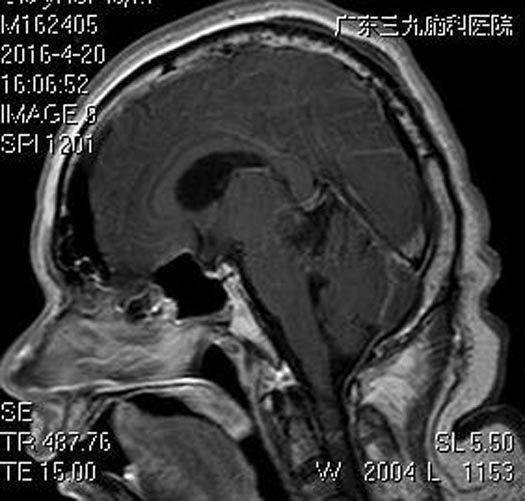

广东三九脑科医院行头颅MR检查显示:右侧小脑幕跨幕上下区示一肿块,大小约为4.0cm×3.8cm×3.6cm;邻近脑组织受压移位,以中脑尤为明显,其内中脑导水管及三脑室受压变窄,幕上脑室系统扩大,考虑脑膜瘤可能性大;头颅CTA检查提示:右侧跨小脑幕上下占位病变内血管丰富,右侧大脑后动脉受压向上移位。

由综合神经外科鲁明主任主刀,在全麻下行右侧跨小脑幕脑膜瘤切除术,术中见肿瘤血供丰富,质中,边界清楚,有完整包膜,肿瘤下压小脑,前内下方压迫脑干,前内上方累及松果体区,全切肿瘤,大脑后动脉、大脑大静脉、脑干等周围重要结构保护完好,手术顺利。术后邱先生耳鸣症状消失,已康复出院。术后病理结果提示:过渡型脑膜瘤WHO I级。